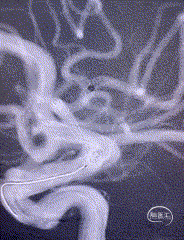

小血管血栓取栓病例

急诊大脑后动脉取栓病例分享

作者:焦伟 冉星堂